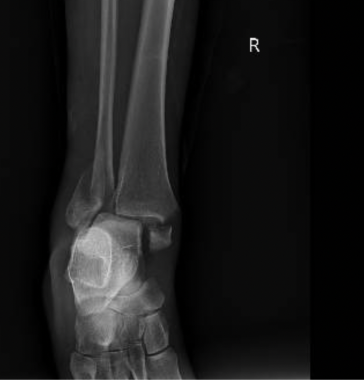

You being an astute physician decide to get an XR:

• Findings of acute bilateral malleolar fracture